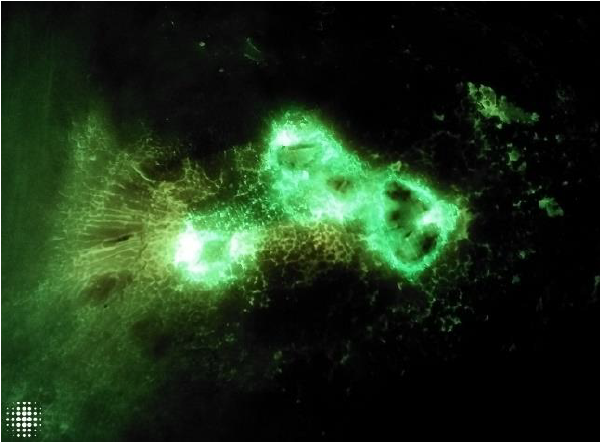

Detection of bacterial fluorescence from in vivo wound biofilms using a point-of-care fluorescence imaging device

Lopez, AJ et al. Int Wound J 2021